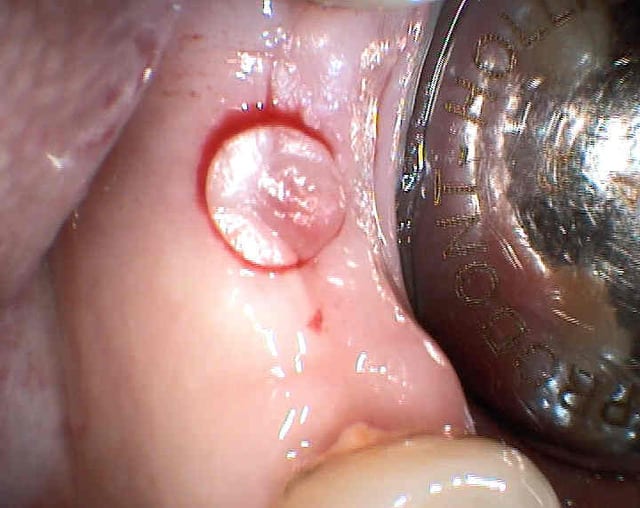

06/08/2010 à 19h07

rien vu de particulier

un exemple d'un boulevard de GA

desole pour les photos mais j'attends la formation

Le sujet a déjà été traité je sais fouilla mais quel est ton instrument de mise à nu de ta tête d'implant.

Pour les bistouris circulaires, il existe une série chez Meisinger qui se monte sur CA. très pratique.